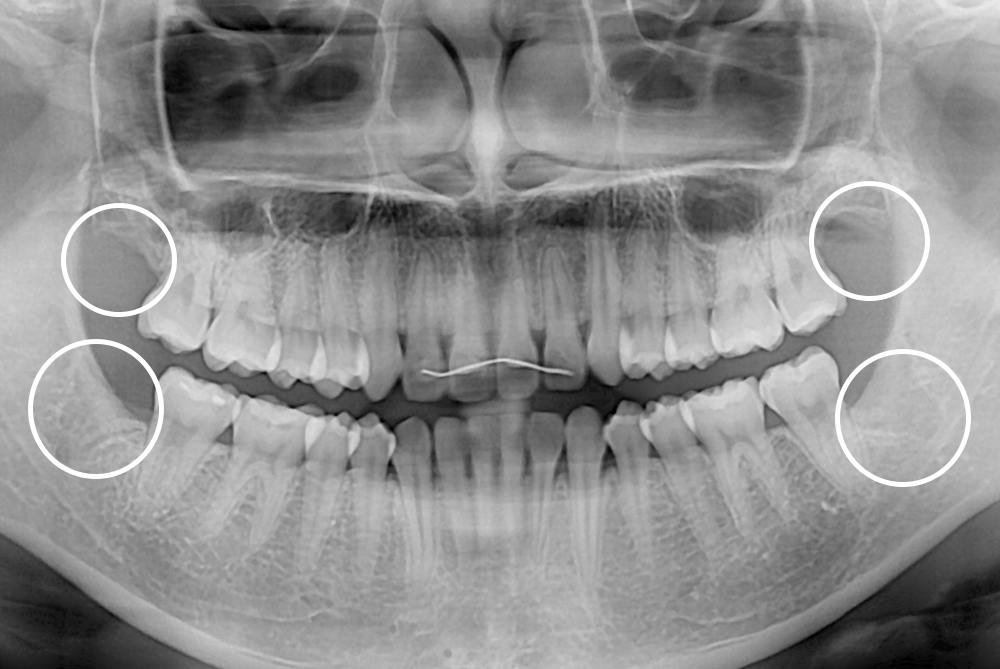

[사랑니] 매복 사랑니 발치

치료전 : 2017-09-05

세종치과는 구강악안면외과학 박사이신 원장님이 발치하는 치과입니다.